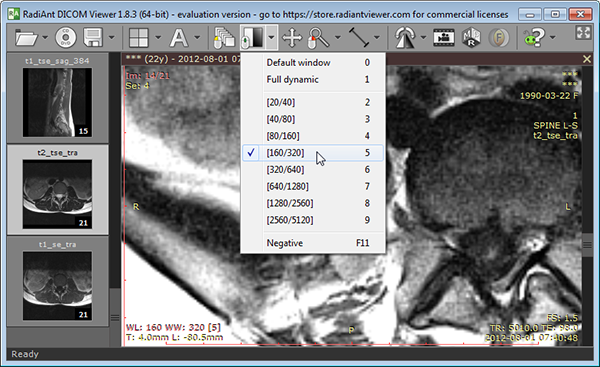

- Added WW/WL presets for modalities other than CT.

- Added WW/WL presets for modalities other than CT.

"- Added WW/WL presets fo modalities other than CT."

where is it? I still see only CT presets...

where is it? I still see only CT presets...

Have a look at the image below :-)

These presets are also available under keyboard shortcuts 2-9.

These presets are also available under keyboard shortcuts 2-9.

Ok. I see... if I load a CT case, Ct presets are offered, whilst if I load an MR case those new presets are available.